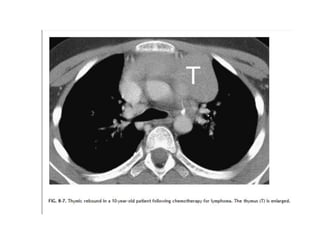

THYMIC HYPERPLASIA

• Thymic hyperplasia, as distinguished from LFH, is defined by an

increase in size of the thymus associated with an otherwise normal

gross and histologic appearance.

• It may be associated with hyperthyroidism (Graves' disease,

sarcoidosis, red blood cell aplasia, and other entities.

• It most commonly is seen in association with recovery from

chemotherapy, stress, or burns, a phenomenon known as thymic

rebound (described below).

• Chest radiographs in adults are usually normal.

• In children, thymic enlargement may be seen.

• CT demonstrates increased thickness of the thymic lobes but an

otherwise normal-appearing thymus

Thymic Rebound

• The thymus involutes during periods of stress (e.g.,

burns, chemotherapy) and may decrease significantly

in size

• the thymus will generally regrow to its original size

within several months of the stressful episode

• The presence of lymph node enlargement in

association with thymic enlargement should suggest

recurrent tumor, while isolated thymic enlargement

should suggest thymic rebound